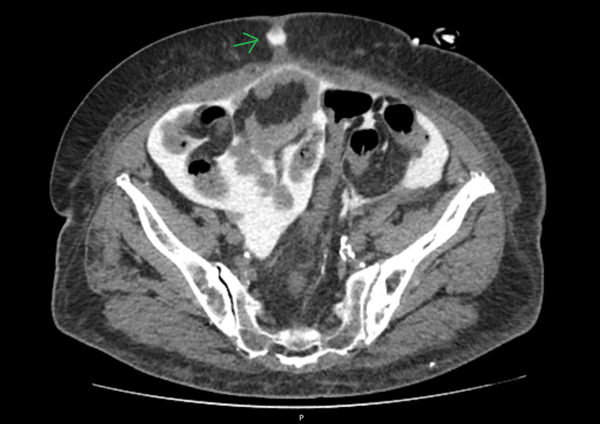

To assess for a possible peri-catheter leak and rule out a catheter fracture, a computed tomography (CT) scan was performed with contrast infusion into the peritoneal cavity (Figure 2 and Figure 3). The protocol included a standard non-contrast CT scan followed by a 2 h dwell of 1.36% glucose dialysate to which 100 ml of contrast was added, comprising a total of 2 liters of infused fluid.

Figure 2. Transversal CT cut

A second CT scan was performed afterward. Imaging showed dialysate drainage through the midline in the periumbilical region, where there was also significant adipose tissue densification. Intraperitoneal pressure was not measured at this time.